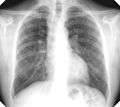

For uncomplicated silicosis, chest x-ray will confirm the presence of small (< 10 mm) nodules in the lungs, especially in the upper lung zones. Using the ILO classification system, these are of profusion 1/0 or greater and shape/size "p", "q", or "r". Lung zone involvement and profusion increases with disease progression. In advanced cases of silicosis, large opacity (> 1 cm) occurs from coalescence of small opacities, particularly in the upper lung zones. With retraction of the lung tissue, there is compensatory emphysema. Enlargement of the hilum is common with chronic and accelerated silicosis. In about 5-10% of cases, the nodes will calcify circumferentially, producing so-called "eggshell" calcification. This finding is not pathognomonic (diagnostic) of silicosis. In some cases, the pulmonary nodules may also become calcified.

Complicated silicosis

Silicosis ILO Classification 2-2 R-R